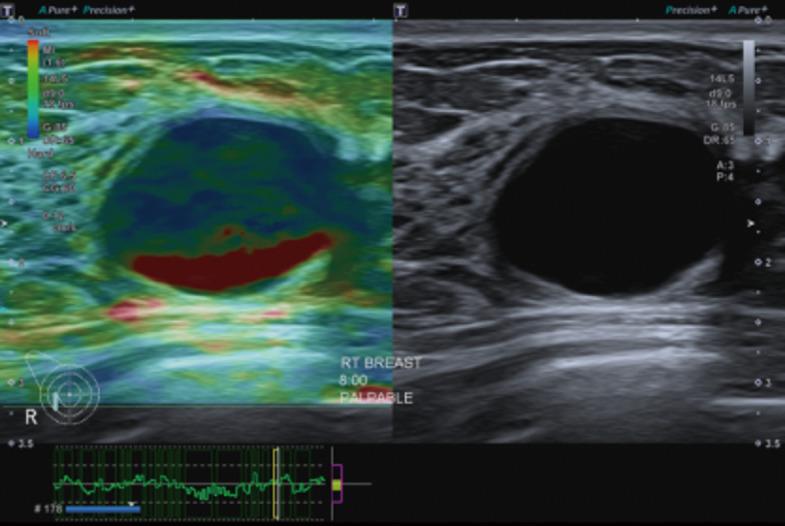

Several new ultrasound tools have been developed to further evaluate breast lesions detected on B-mode ultrasound. Strain elastography (SRE) was developed to assess the likelihood of malignancy of lesions based on their stiffness. This has been incorporated into the latest edition of the American College of Radiology (ACR) Breast Imaging Reporting and Data System (BI-RADS) lexicon and atlas. However, no agreed cut-off stiffness values have been established to distinguish benign from malignant lesions making the translation into routine clinical practice difficult. Superb microvascular imaging (SMI) was developed to better evaluate the vascularity within sonographic lesions and assess their likelihood of malignancy. However, there is also no agreed cut-off value for vascular index (VI) to distinguish between benign and malignant lesions. MicroPure was developed to better visualize and evaluate calcifications seen on ultrasound. Its effective use in breast screening and evaluating the calcifications detected for likelihood of malignancy have not been established. This article describes the original intended uses of these applications and reviews the studies evaluating them, showing the varying success of the translation of these tools into routine clinical practice. Also described are some other uses of these tools for which they were not originally intended. This illustrates the importance of being perceptive to alternative uses of imaging tools in their translation from bench to bedside.

已经开发了几种新的超声工具,以进一步评估在B型超声检查中发现的乳腺病变。应变弹性成像(SRE)是为了根据病变的硬度评估其恶性可能性而开发的。这已被纳入美国放射学会(ACR)乳腺影像报告和数据系统(BI-RADS)词汇表和图谱的最新版本。然而,尚未确定用于区分良性和恶性病变的一致的硬度临界值,这使得其难以转化为常规临床实践。超级微血管成像(SMI)是为了更好地评估超声病变内的血管情况并评估其恶性可能性而开发的。然而,对于区分良性和恶性病变的血管指数(VI)也没有一致的临界值。MicroPure是为了更好地显示和评估超声所见的钙化而开发的。其在乳腺筛查中的有效应用以及评估检测到的钙化的恶性可能性尚未得到证实。本文描述了这些应用的最初预期用途,并回顾了评估它们的研究,展示了这些工具转化为常规临床实践的不同成功程度。还描述了这些工具的一些并非最初预期的其他用途。这说明了在成像工具从实验室到临床的转化过程中,敏锐地感知其替代用途的重要性。